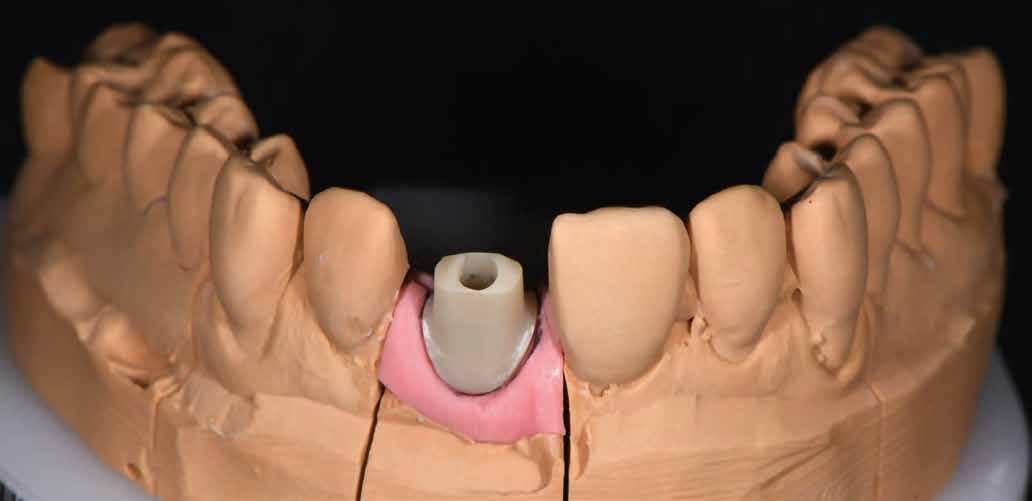

építményhez gyári Camlog titánbázist használtunk, amit előzetesen befedtünk DCMhotbond fusio connect spray-vel. A titánbázis felületi kondicionálásához alkalmazott anyag kiváló, résmentes és tartós kötési alapot teremt a bázis és a rá készülő cirkon konstrukció között1. A cirkónium-dioxid egyedi felépítmény tervezését primer teleszkóp koronaként választottuk ki a CAD-szoftveres lehetőségek tárából. A felső mintát a beszórt titánbázissal ínymaszkkal és anélkül is beszkenneltük, akárcsak az antagonista mintát. A titánbázist hárompontos vonatkoztatással illesztettük a digitális mintába, majd megállapítottuk a behelyezési irányt és az illesztő paramétereket (7–13. képek).

Tervezés és kivitelezés a laboratóriumban

Az implantátumról készült lenyomat, valamint az alginát antagonista fertőtlenítése után szuperkemény gipszből az előírások szerint elkészültek a minták. A felső mintát a technikai implantátum körül levehető ínymaszkkal készítettük. SAM-arcív segítségével habituális okklúzióba helyeztük a mintákat. A felső mintát előkészítettük a digitális tervezéshez, enyhén megformáltuk az emergenciaprofilt, hogy tökéletes legyen a rózsa-fehér esztétika. A fogszínt – a pácienssel történt egyeztetést követően – dokumentáltuk.

Digitális tervezés

A mintát beolvastuk (D1000, 3Shape), majd megterveztük a munkát (3Shape Dental System) (6. kép). A fel -

Az 11-es fogat tükrözzük, majd megfelelő pozícióba helyezve kialakítjuk helyes méretét. Most elkészíthetjük alá az egyedi felépítményt. Ehhez a vállat illesztjük a gingiva lefutásához, az alá kb. 0,5 mm-rel elhelyezve (14. kép). A gingiva-rész adatállománya tetszés szerint jeleníthető meg, láthatóan, vagy akár transzparensen is (15. kép). A szabadkézi eszközzel egyedileg alakíthatók ki az egyéni fej dimenziói (16. kép). Ehhez újra és újra rávetítjük a tükrözött fogat a kész konstrukcióra. Palatinálisan csak a szinterezést követően redukálom a felépítményt (17. kép). A kész konstrukcióra újra rávetítjük a tükrözött fogat és az ínymaszkot, a terv ellenőrzésére (18–19. képek). A kész tervet most rávetítjük egy nyers cirkontömbre, elhelyezzük a megfelelő